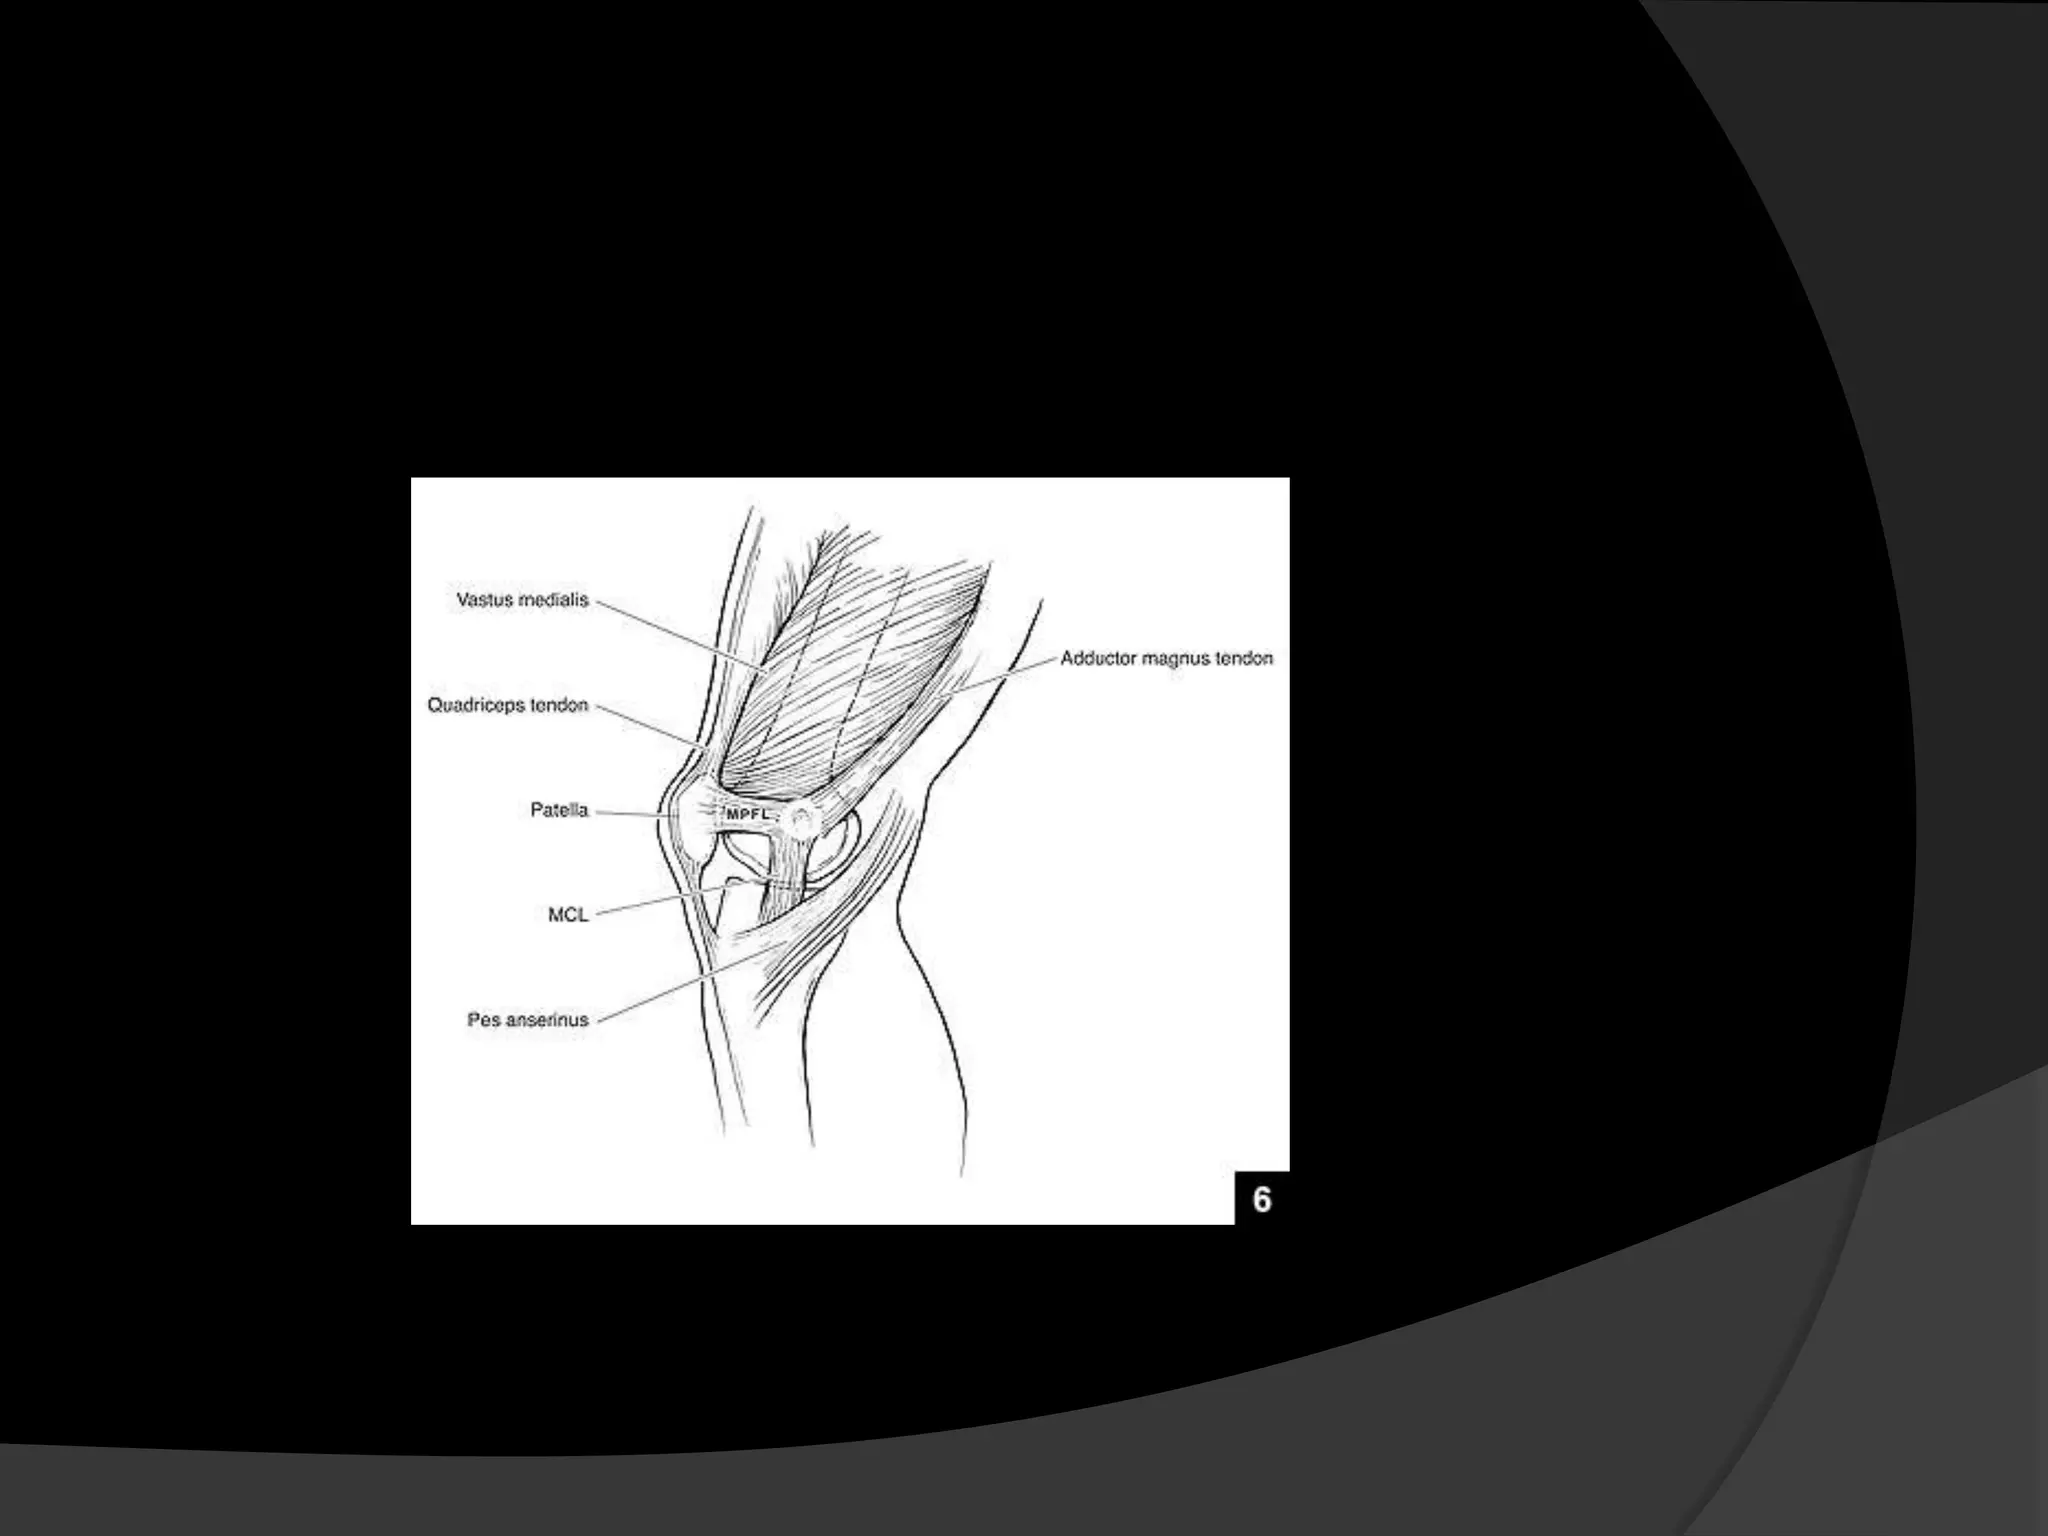

Anatomy

It extends between the superomedial pole

of the patella to the anterior aspect of the

medial epicondyle

The vertical distance from the superior pole

of the patella to the top of the medial

patellofemoral ligament averages about 6.1

mm.

The distal border of the VMO muscle

attaches along the majority of the proximal

medial edge of the MPFL

Steensen RN et al, Am J Sports Med. 2004;32:1509-1513.